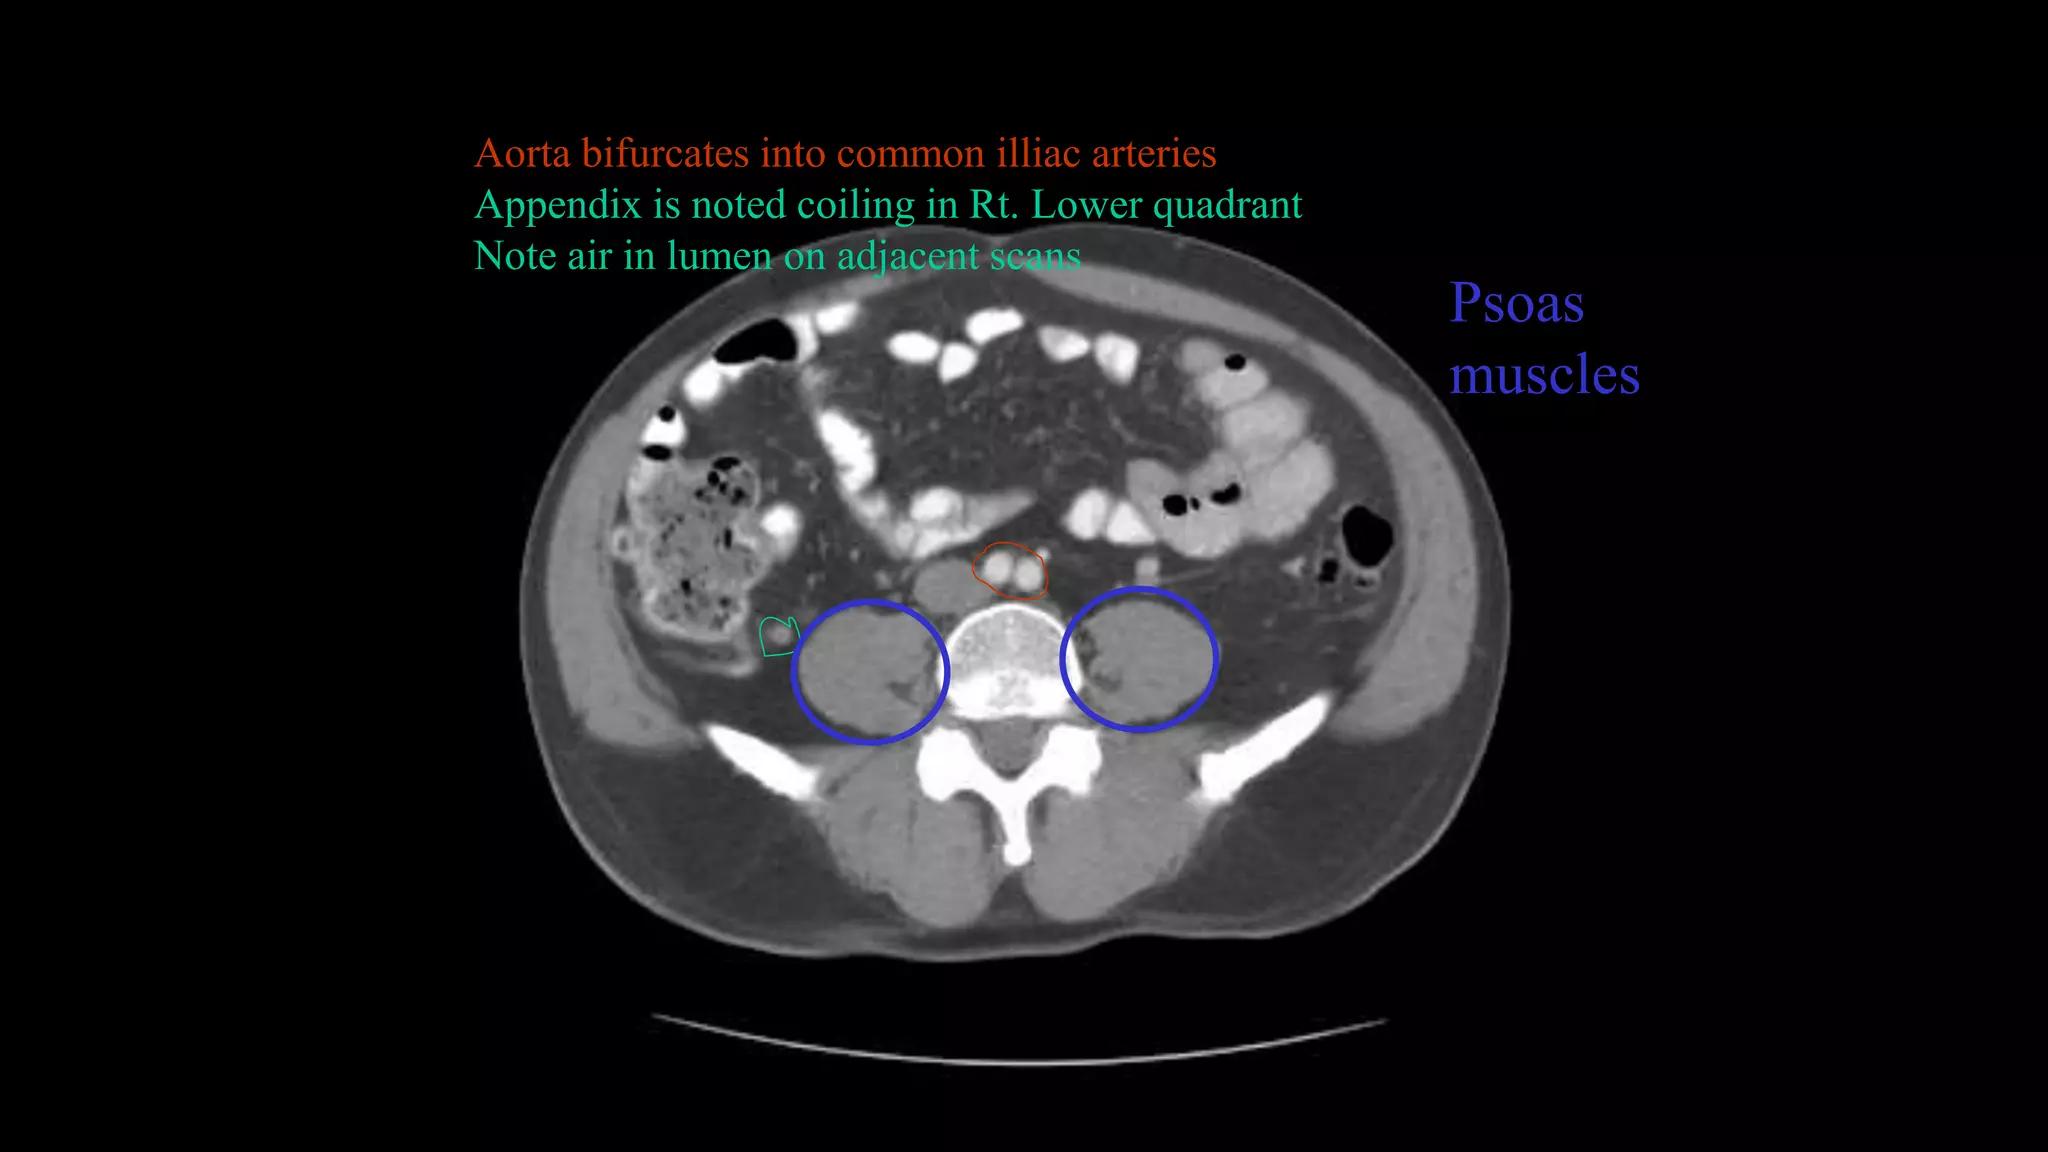

Aorta bifurcates into common illiac arteries

Appendix is noted coiling in Rt. Lower quadrant

Note air in lumen on adjacent scans

Psoas

muscles

Aorta bifurcates intocommon illiac arteries Appendix is noted coiling in Rt. Lower quadrant Note air in lumen on adjacent scans Psoas muscles